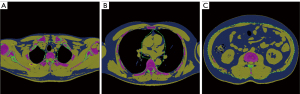

Chest LDCT images in QCT format were post-processed. The adipose tissue was measured with the Tissue Composition Module of QCT software (Mindways Software Inc., Austin, TX, USA). Using QCT software, adipose tissue was automatically segmented and mapped in blue color, and the outer contour of abdominal wall was semi-automatically outlined on the single L2/3 intervertebral space slice. The abdominal total adipose tissue (TAT) and VAT areas (cm2) were automatically calculated, and TAT areas minus VAT areas were equal to SAT areas. The IAT measurements were retrospectively performed at the single slice of each intervertebral space level in the chest because the optimal level of IAT measurement was not yet clear. A well-trained physician (L.H.Z.) manually outlined the outer contour of mediastinum, and IAT areas (cm2) were automatically calculated by the QCT software (Figure 1).